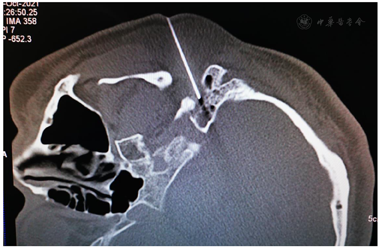

鉴于MS与HFS的临床表现有高度相似之处,我们设想,用于治疗HFS的面神经射频技术有望用治疗MS。经报请医院伦理委员会讨论通过(LS2019-013),决定给患者施行双侧面神经射频治疗。术前向患者及其家属详细交待操作经过和可能出现的轻度面神经麻痹并发症,取得知情同意并签署书面知情同意书后,嘱患者右侧向上侧卧于CT台上,安置血压、心电图、脉搏血氧饱和度监测设施并给予鼻导管吸氧,并在耳垂前后放置CT定位定位栅(图2)。用鼻旁窦模式拍摄头颅定位像,并对乳突区进行层厚3 mm轴位扫描,选取含茎乳孔且无颞骨鼓部骨质阻挡的CT层面作为穿刺层面,并在该层面上设计穿刺路径:以右侧茎乳孔为穿刺靶点,用CT自带测量工具软件由右茎乳孔向前上拉直线,该线与皮肤的交点即为穿刺点,测量穿刺深度(穿刺点至靶点的距离)和穿刺角度(穿刺路线与矢状面的夹角)(图3)。对穿刺点进行局部麻醉,用长度为10 cm、裸露端为5 mm的7号射频针在CT引导下穿刺至靶点(图4)并CT扫描三维重建观察确认(图5),随后用低频(2 Hz)电流进行运动神经刺激测试,0.5 mA电流电刺激即能诱发出右侧面肌出现与电刺激相同频率痉挛性抽动,见视频,给予65℃标准射频消融,同时嘱患者鼓腮、闭眼,射频第27秒鼓腮漏气,右眼不能紧闭,即停止射频,结束手术,见视频。2 d后同样于CT引导下行左侧茎乳孔穿刺面神经射频消融治疗(图6,图7,图8)。